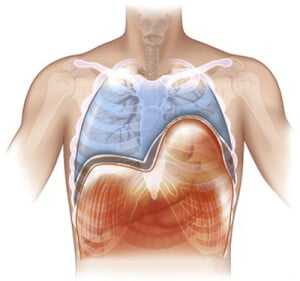

Диафрагма (diaphragma от греч. — перегородка), или грудобрюшная преграда — это куполообразная перегородка, которая разделяет грудную и брюшную полости. Выделяют центральную сухожильную и краевую мышечную части диафрагмы. Сокращаясь и расслабляясь диафрагма принимает участие в акте дыхания.

Релаксация диафрагмы - одностороннее стойкое высокое расположение диафрагмы, сохраняющей свою непрерывность и прикрепление в обычных местах.

В основе заболевания — повреждение диафрагмального нерва, при котором диафрагма расслабляется и не сокращается (т.е. наступает её релаксация). Так как в брюшной полости положительное давление, а в грудной клетке в большей части отрицательное, то органы брюшной полости давят на релаксированный купол диафрагмы. Таким образом, купол диафрагмы поднимается выше обычного, сдавливая собой соответствующее легкое. Часто заболевание так и называют — релаксация купола диафрагмы.